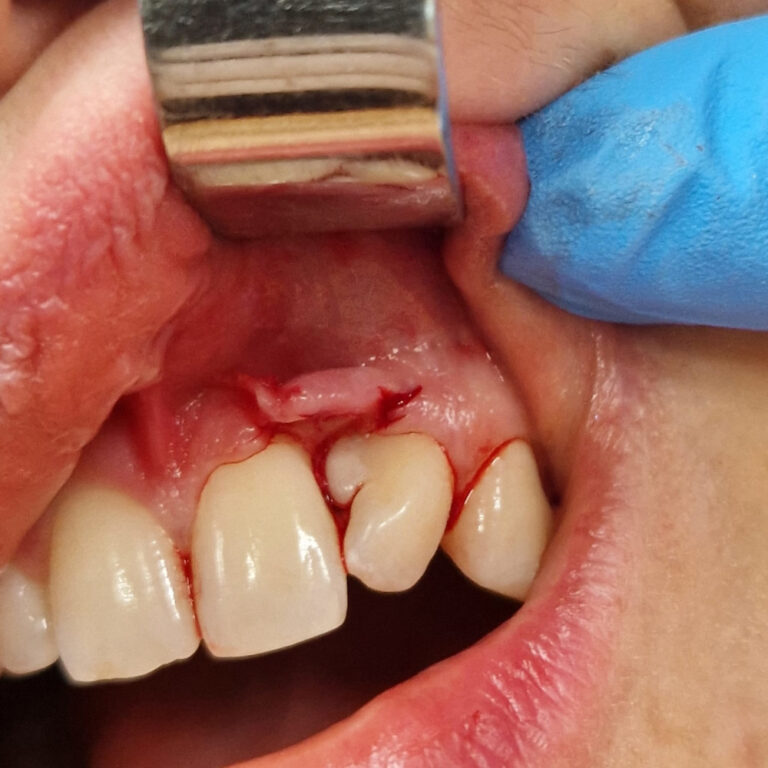

Przykłady zabiegów

Ortodoncja CBCT

Leczenie chirurgiczno-ortodontyczne wad zębowych z zastosowaniem tomografii spiralnej CBCT w naszej klinice.